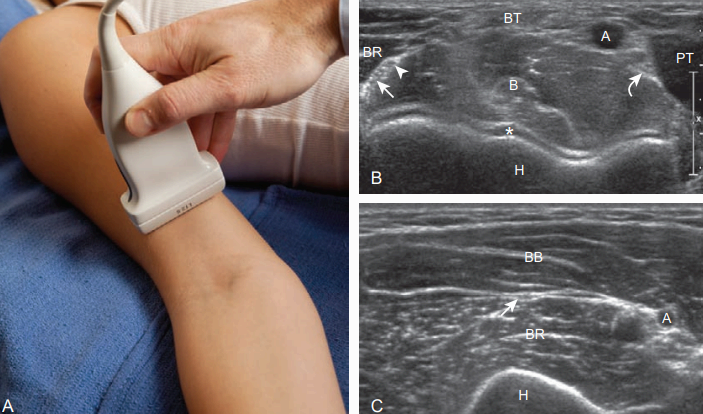

팔꿈치 앞쪽검사(anterior) 팔꿈치는 펴고, 손바닥을 위로 향하게 한다. 앞쪽에서 일차적으로 검사할 구조물은 위팔근, 먼쪽위팔 두 갈래 근(biceps brachii), 정중신경과 앞쪽 팔꿈치관절오목이다. 탐촉자를 팔꿈치관절보다 약간 위에 시상면으로 놓으면, 위팔근이 낮은 에코로 보이며, 높은 에코의 섬유지방 사이막(fibroadipose septa)이 함께 보인다. 앞쪽 관절오목을 검사할 때는 초점구역을 위팔뼈 앞쪽의 뼈겉질(cortex)이 보이도록 조절해야 한다. 갈고리오목(coronoid fossa)과 이보다 더 작은 노뼈오목은 먼쪽 위팔뼈에서 오목하게 보인다. 정상적으로 이들 오목 내에는 세모꼴의 피막 내 지방덩이가 있어서 높은 에코로 관찰된다.

도르래의 우리연골(hyaline cartilage)이 낮은 에코로 보이고, 몸 쪽 자뼈갈고리돌기(coronoid process)의 특징적인 뼈윤곽(bone contour)이 보인다. 위팔근을 검사할 때는 세로면과 가로면 영상에서 몸쪽자뼈의 부착 부위까지 아래쪽으로 추적해 간다.

먼쪽먼쪽 위팔 두 갈래 힘줄은 위팔근 힘살(belly)의 표층에 있다. 먼쪽 위팔 두 갈래 힘줄은 찾기 힘든 경우가 있으며, 가로면으로 검사를 시작하면 도움이 된다. 탐촉자를 위에서 아래로 이동하면 위팔 두 갈래 근의 근육 힘살이 점점 가늘어지고 위팔근의 표층에서는 힘줄을 확인할 수 있다. 위팔동맥은 쉽게 찾을 수 있으며, 표식자(landmark)로 이용할 수 있다. 위팔 두 갈래 힘줄은 위팔동맥의 가쪽에 보이고, 정중신경이 많은 점 모양 또는 벌집모양(speckled or honeycomb appearance)으로 위팔동맥의 안쪽에 위치한다.

위팔 두 갈래 힘줄이 보이면 탐촉자를 90도 돌려 세로방향에서 검사한다. 먼쪽 위팔 두 갈래 힘줄은 비스듬히 주행하면서 탐촉자로부터 멀어지기 때문에 힘줄이 종종 비등방성 인공물에 의해 낮은 에코로 보일 수 있다. 이를 줄이려면 초음파빔과 힘줄이 수직이 되도록 해야 하며, 이를 위해 탐촉자로 비스듬하게 아래쪽으로 압력을 가한다. 초음파장비에 따라 빔을 비스듬하게 조정할 수 있는 기능을 가진 것도 있다.

먼쪽 두 갈래 힘줄의 노쪽결절 부착부위는 팔꿈치를 여러 각도로 굽히고 편 상태에서 검사를 시행한다. 정중신경은 위팔동맥의 안쪽에서 보이고 아래에서는 원엎침근의 위팔뼈와 노뼈머리(radial head) 사이를 주행한다. 정중신경은 가로단면에서 낮은 에코의 굵은 신경다발(nerve fascicles)과 높은 에코의 결합조직(connective tissue)에 의해 벌집모양으로 보인다. 원엎침근의 자뼈갈래는 정중신경과 자뼈동맥 사이에 위치한다.